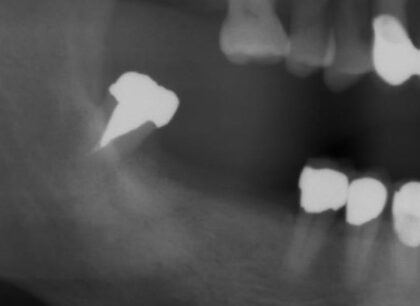

術前レントゲン

術前レントゲン

術後レントゲン

術後レントゲン

| 主訴 |

折れている歯を眠っている間に完全無痛でインプラントをして欲しい。インプラント手術自体をいかに痛みや不安がなく治療ができる医院がないかを探していた。抜歯と同日のインプラント手術を「完璧にできる」という歯科医師に治療してもらいたいと思っている。 |

|---|---|

| 年代・性別 | 60代 男性 |

| 治療部位 | 左下7 |

| 治療費用 |

インプラント手術料 300,000円 |

| 手術回数 | 2回 |

| 治療期間 | 4ヶ月 |

| 手術時間 | 90分 |

| 治療回数 | 5回 |